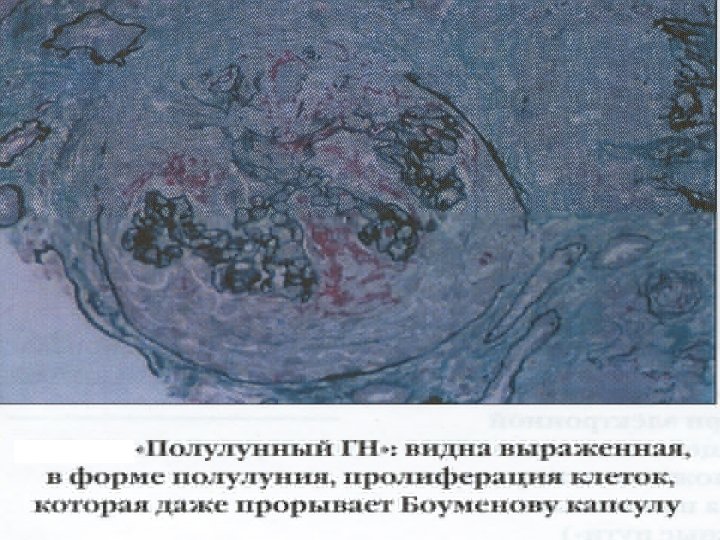

Морфологические варианты нефропатий § § § Минимальные изменения клубочков Фокально-сегментарный гломерулосклероз Мембранозная нефропатия Мезангиопролиферативный гломерулонефрит Мезангиокапиллярный (мембранопролиферативный) гломерулонефрит Диффузный пролиферативный гломерулонефрит Экстракапиллярный гломерулонефрит Фибропластический (склерозирующий) гломерулонефрит Диабетическая нефропатия Амилоидоз почек Гипертонический нефроартериолосклероз

Нормальный клубочек Постстрептококковый гломерулонефрит: много клеточных ядер вследствие пролиферации клубочковых клеток